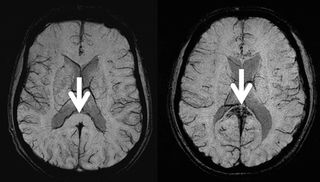

Higher repetitive head impacts in adult soccer players were associated with lower fractional anisotrophy and a higher orientation dispersion index in the frontal lobe, orbitofrontal cortex, and the parietal lobe, according to diffusion MRI findings to be presented at the Radiological Society of North America (RSNA) conference.